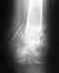

Был тройной перелом голени. Операция была сделана крайне неудачно. Край кости выпирает. Хирург ,проводивший операцию предлагает просто его отпилить. На консультации в другой клинике предлагают извлечь штифт и поставить аппарат Елизарова. Страшно.Подскажите пожалуйста возможно ли исправить ситуацию заменив штифт и правильно соединив обломки. Снимки прилагаю.

Возможно я плохо изложила свою проблему.У меня был перелом обеих костей голени со смещением. 13 января был установлен штифт.Операция была не совсем удачная т.к.сильно выступает острый обломок б.берцовой кости. Очень некрасиво и есть опасность разрыва кожи.

Три ортопеда к которым я обращалась за консультацией считают, что такой результат неприемлем. необходимо извлечь штифт и установить аппарат Илизарова.

Посмотрите снимок.Можно ли оставить всё в таком виде и впоследствии подкорректировать?